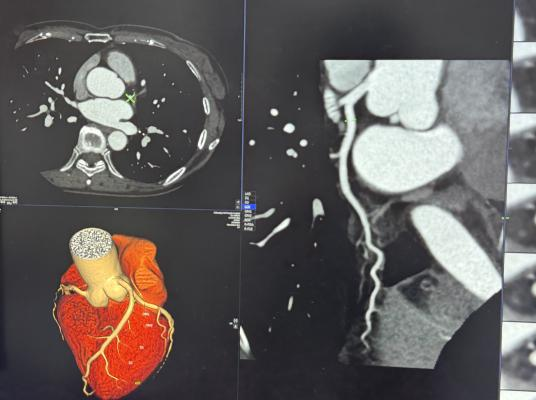

冠脉CTA全称“冠状动脉CT血管成像”,是一种无创检查方法。可将其理解为对心脏血管进行“高清三维成像”,检查时,经手臂静脉注射少量含碘显影剂,再通过CT扫描获取图像,由计算机重建生成血管影像,即可清晰显示血管形态、走向,以及是否存在斑块或狭窄。整个过程无明显痛感,通常耗时10至15分钟。